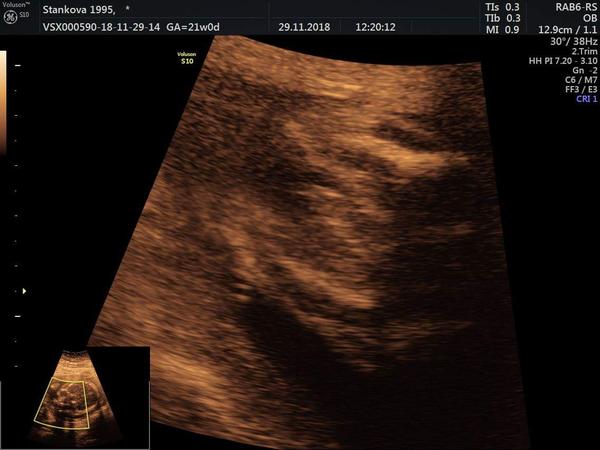

My dostali takovou fotecku s tim, ze to bude kluk (fotka z 21.tydne) .... Ve 33. nebo 34. tydnu (ted nevim) jiste na dr rekl, ze to kluk bude (tak snad, do porodu to jiste neni) ..... Ale pro uklidneni, kamaradce 3x rekli, ze to bude kluk a maji Anicku 🙂 jeste se to dozvedet muzes 🙂